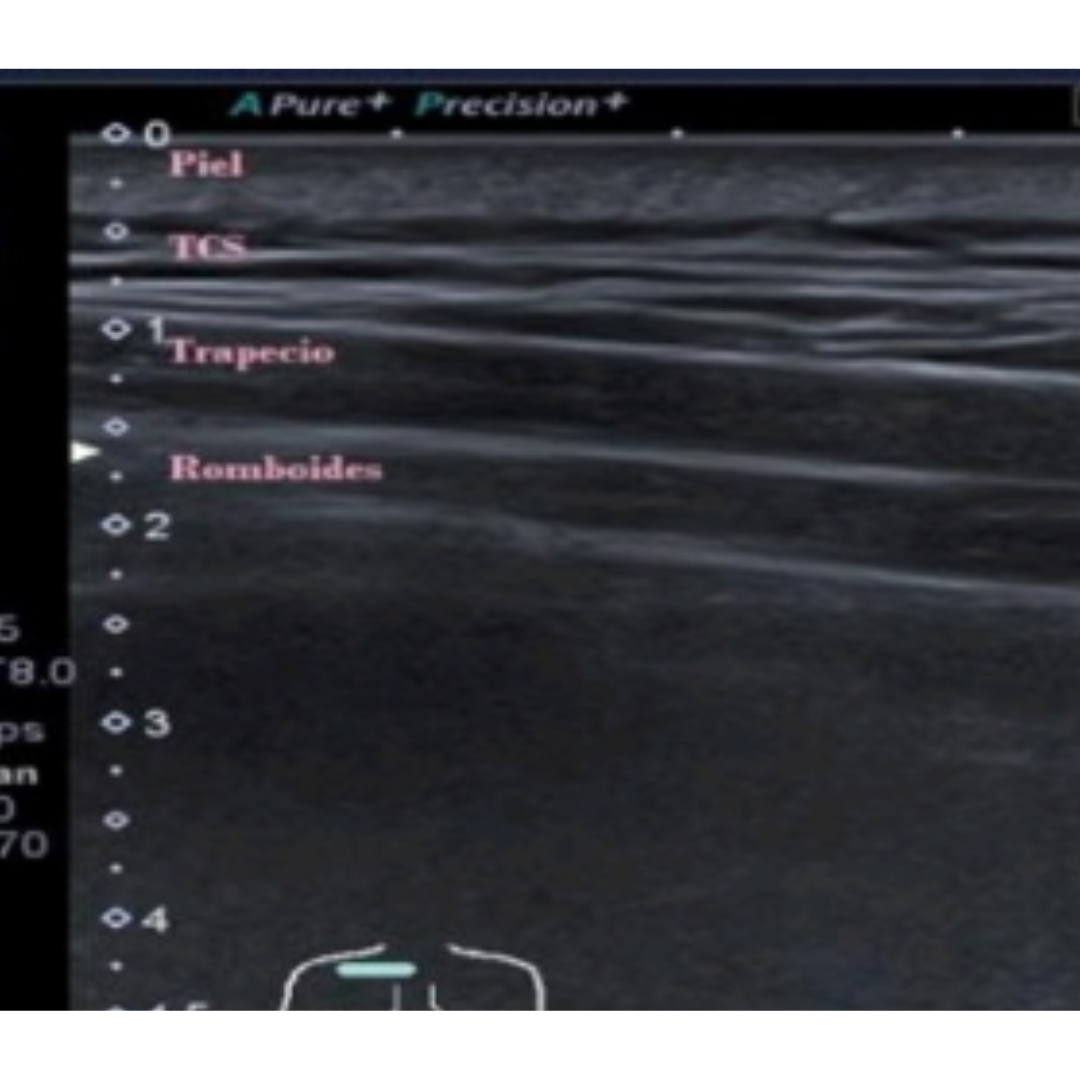

Imagen 5: Los romboides se pueden encontrar entre la columna vertebral y el borde medial de la escápula bajo el trapecio. De superficial a profundo: piel - tejido celular subcutáneo – trapecio – romboide.